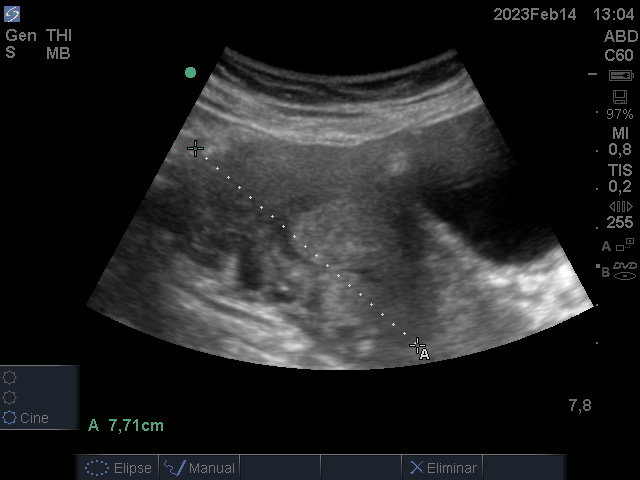

Se realiza ecografía renal y vesical en Consulta de médico de Cabecera

Hallazgos ecográficos

Riñones de tamaño y ecogenicidad normal, con relación cortico sinusal conservada.

Vejiga bien replecionada sin ecos en su interior.

Útero aumentado de tamaño heterogéneo, con áreas sólido quísticas de bordes irregulares.